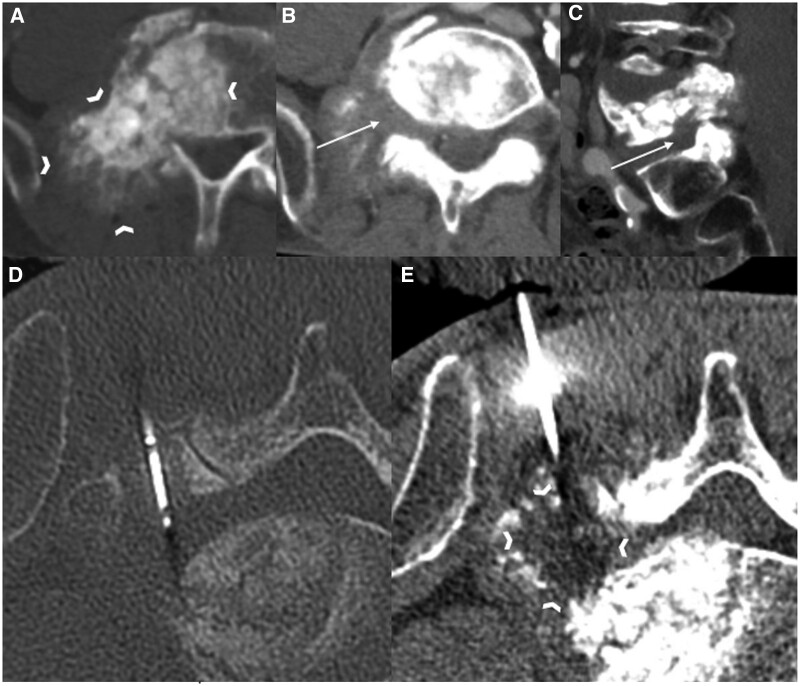

Abstract Image